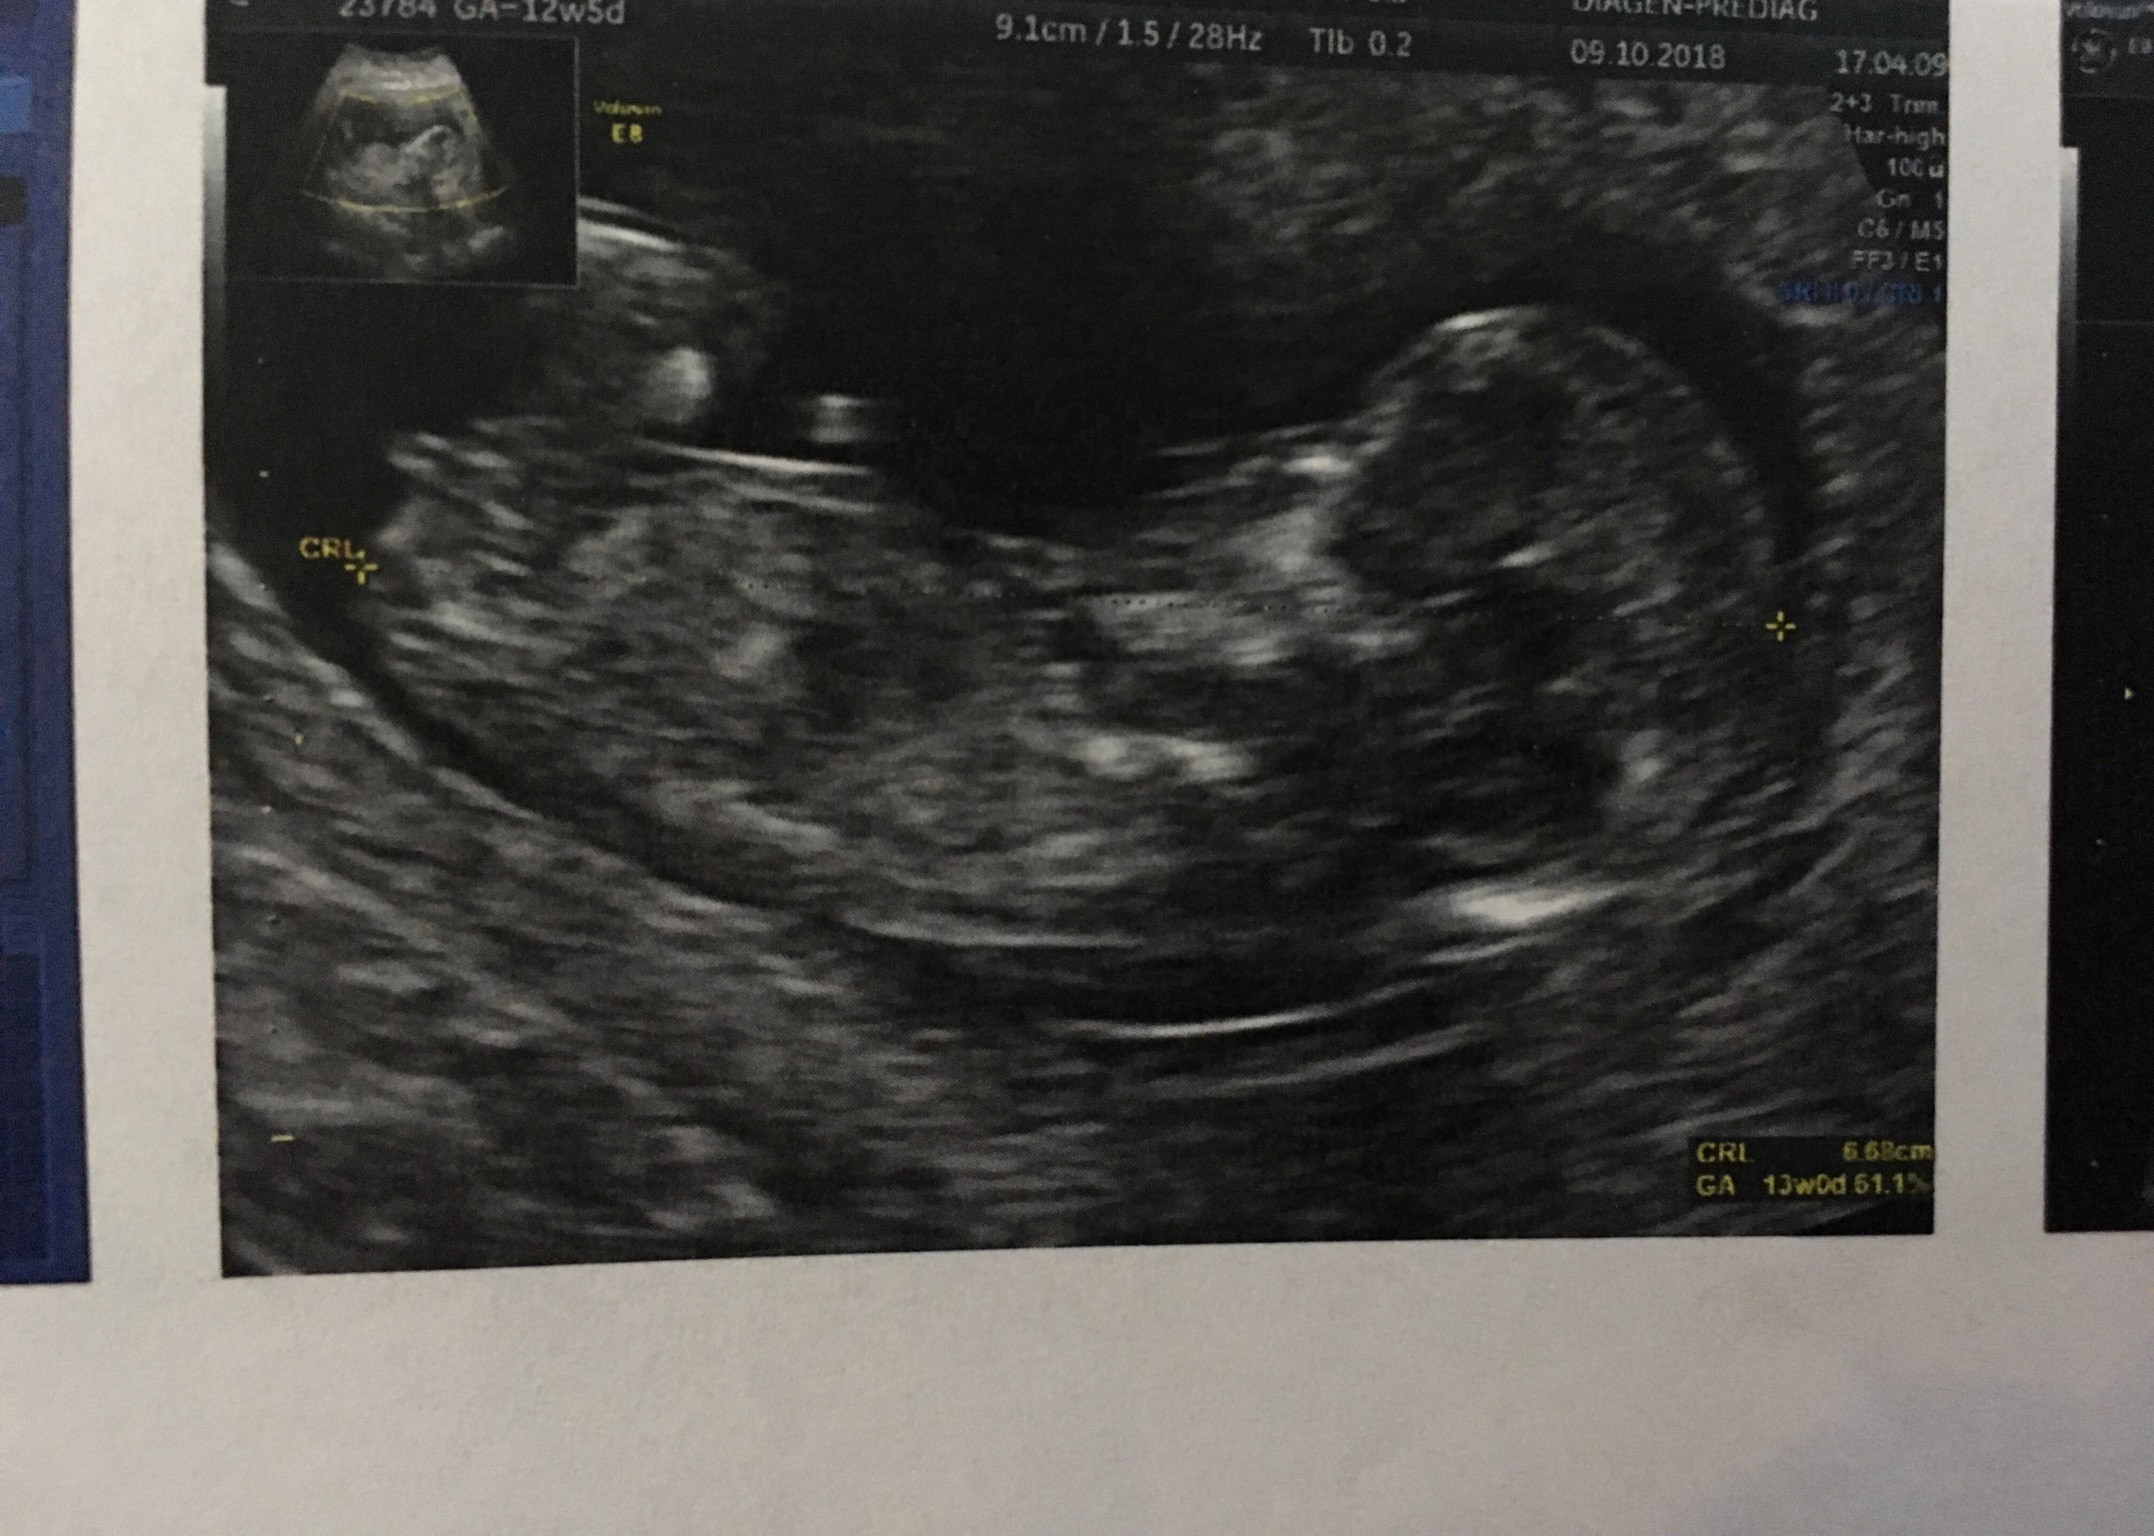

Witam w 19 tygodniu ciąży dowiedziałam się ze będę miała dziewczynkę w 20 tyg okazało się jednak , że to chłopak. Sama już nie wiem bo na jednym usg widać na pewno dziewuche a na drugim chłopca. Może to pempowina ?? Może ktoś mi pomoże rozwiązać ta zagadkę

no nic , zobaczymy na kolejnym USG. To doswiadczona Pani wiec chyba wie co mówi a ja ogladam zdjęcia pod każdym kątem i szukam śladów kobiecych